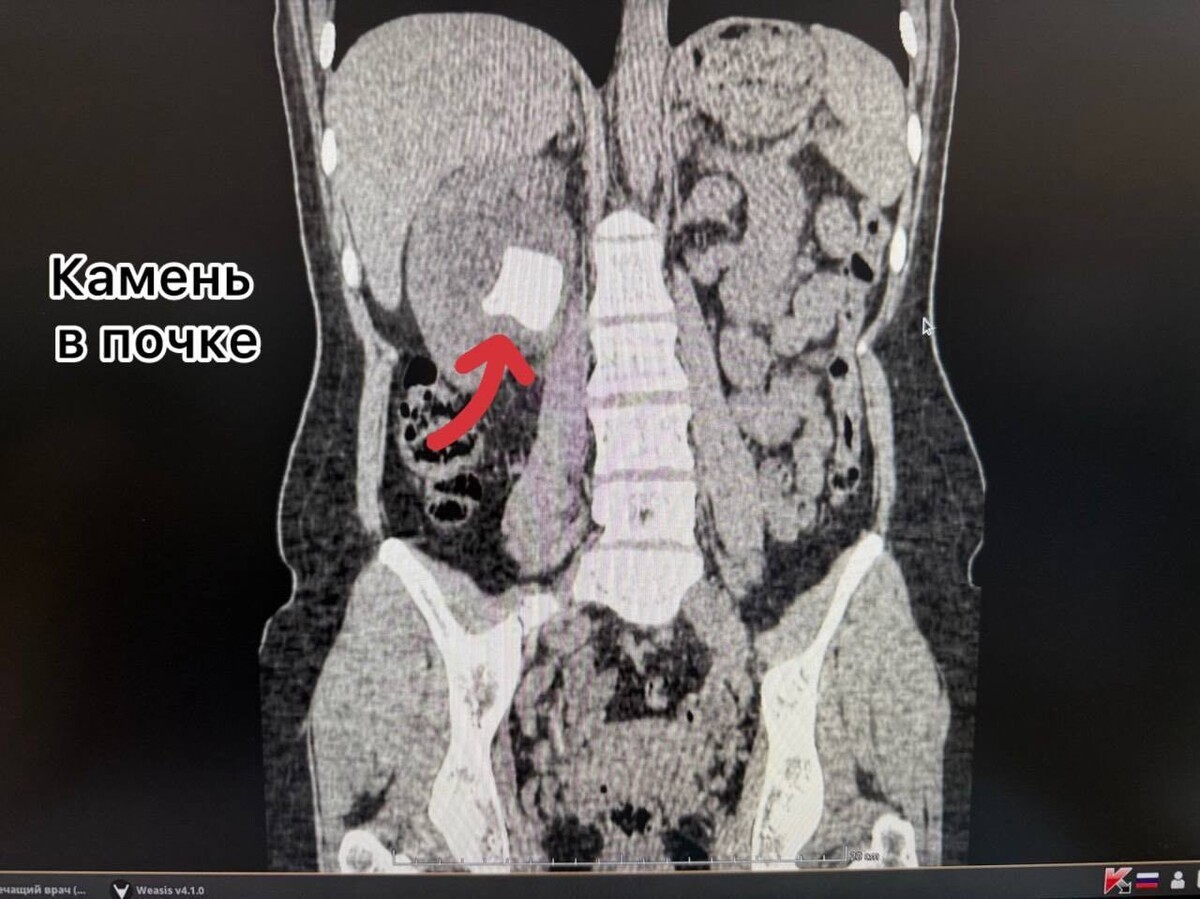

За это время на нём, как на каркасе, отложились соли. Результат — крупные камни образовались и в почке, и в мочевом пузыре, а сам стент превратился в плотную «каменную» структуру.

• Удалить большой камень из почки.